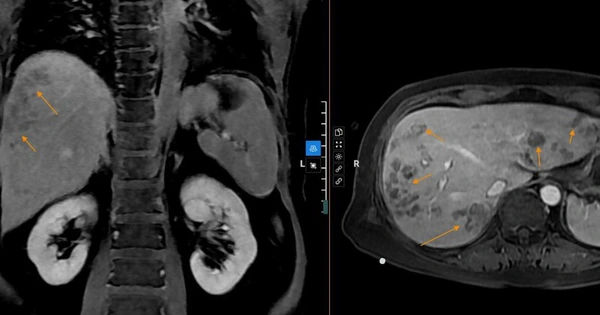

Đã nhập viện với triệu chứng vàng da, vàng mắt và đau bụng, người đàn ông này bị phát hiện có sán lá gan đang hoạt động trong cơ thể Đây là một trường hợp đáng lo ngại và cần được điều trị kịp thời để...